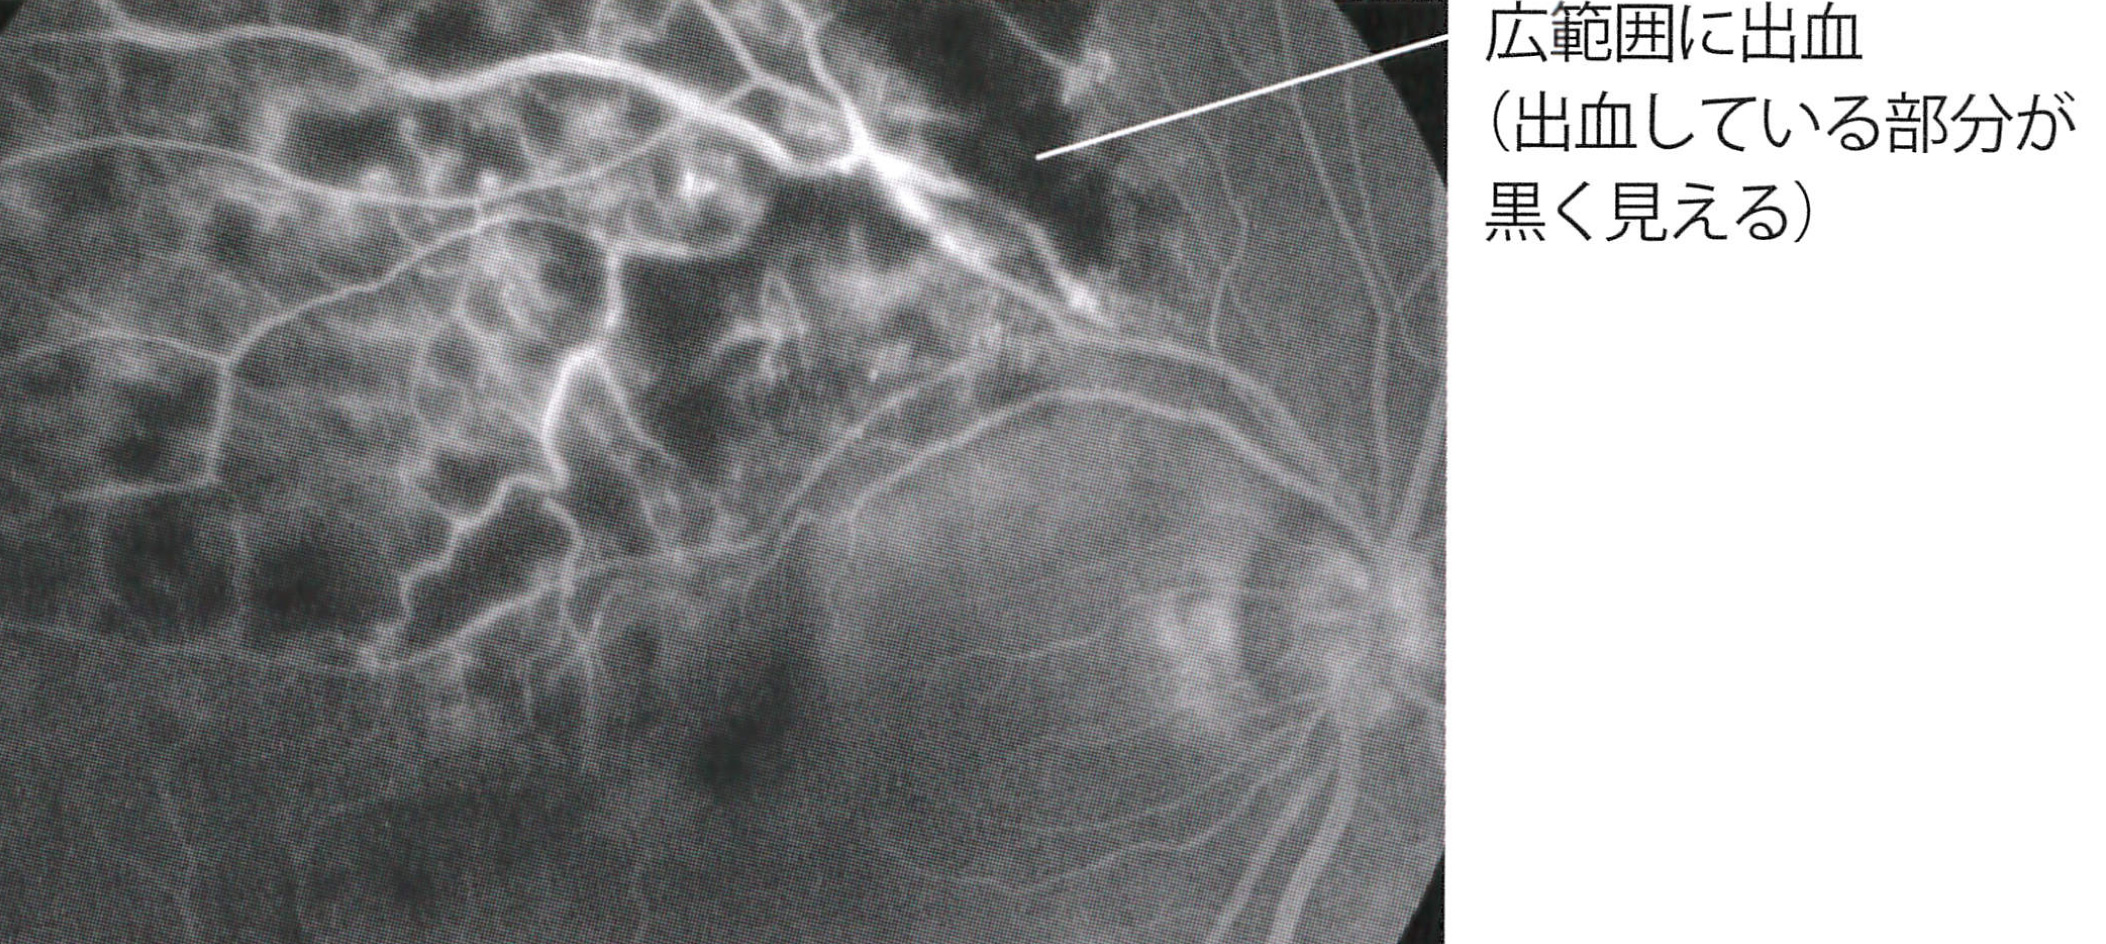

フイルムの役目をする網膜の静脈がつまってしまい、網膜の中心部である黄斑(おうはん)がむくんだり(浮腫)、網膜出血を起こす病気です。視力低下や見たいものが歪んで見えたり、視野障害を生じます。中心の静脈がつまるタイプの網膜中心静脈閉塞症では、硝子体出血や血管新生緑内障を合併することがあります。蛍光眼底造影検査や網膜断層検査(OCT)により、病態、病状の進行を把握します。

網膜静脈閉塞症